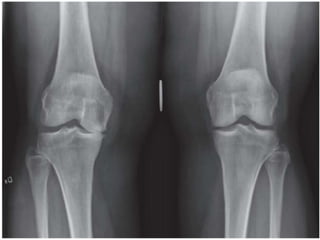

 BLOOD TESTS: NORMAL

 RADIOLOGICAL FEATURES:

◦ CARTILAGE LOSS

◦ SUBCHONDRAL SCLEROSIS

◦ CYSTS

◦ OSTEOPHYTES